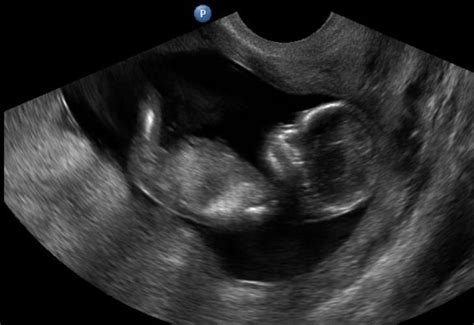

A terhesség korai jelei általában ugyanazok, akár egy vagy több magzat fogant meg. A Cleveland Clinic szerint 250 terhességből egyben lesz ikrekkel várandós a kismama. A legtöbb esetben a terhesség korai szakaszában ugyanazokat a tüneteket tapasztalja, mintha egyetlen gyermeket várna. Az American Pregnancy Association szerint attól nem kell tartani, hogy a reggeli rosszullétek kétszeres erősségűek lennének csak azért, mert két magzat növekszik. A koraterhességi rosszullétek kifejezettebbek, gyakori a kétoldali petefészek-ciszta. Rendszerint már az első trimeszter közepe táján végzett ultrahang-vizsgálat igazolja a többes fogamzás tényét. Fontos azonban megemlíteni, hogy az embriók egy része ebben a kezdeti időszakban elhal, felszívódik, és a későbbiekben csak a másik magzat fejlődik tovább. A nyolcvanas években, az ultrahangos vizsgálatok fejlődésének is köszönhetően jöttek rá az orvosok, hogy az ikerterhesség sokkal gyakoribb, mint korábban hitték. Azonban az esetek zöménél csupán egy gyermek jön a világra, a másik, fejletlenebb magzat a terhesség korai szakaszában elhal, és szinte nyomtalanul felszívódik a méhben. Az eltűnő iker vagy fantomiker szindróma előfordulásával kapcsolatban még mindig sok a kérdés. Valódi fantomiker-szindrómának az orvostudomány azt nevezi, amikor a terhesség nagyon korai szakaszában, a hólyagcsíra beágyazódásáig tűnik el az egyik iker, az embrió elvesztését a későbbi szakaszban méhen belüli elhalásnak hívják. A fantomiker jelenség pedig nem vetélés, mert a fantomikrek nyomtalanul felszívódnak, a terhességre és a fogamzóképességre nem ártalmasak.

A prognózis nagyban függ az ikerterhesség típusától. A kétpetéjű ikrek külön lepénnyel tapadnak és külön burokban fejlődnek (biamniális, bikoriális terhesség, amnion = burok, korion = lepény). Ennek megfelelően fejlődésük is jobban biztosított. Az egypetéjű ikrek fejlődhetnek külön burokban, táplálkozhatnak külön lepényből (biamniális, bikoriális terhesség). Máskor külön burokban fejlődnek, de azonos lepényből táplálkoznak (biamniális, monokoriális terhesség). Az egypetéjű ikreknél azonban gyakoribb a közös méhlepény, részben, vagy teljesen közös magzatburokkal.